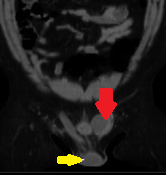

Κόκκινο βέλος — Εκτοπισμένος όρχις στην αριστερή βουβωνική χώρα. Κίτρινο βέλος — Δεξιός όρχις εντός οσχέου (Ευγενική παραχώρηση Dr. V. Penopoulos)